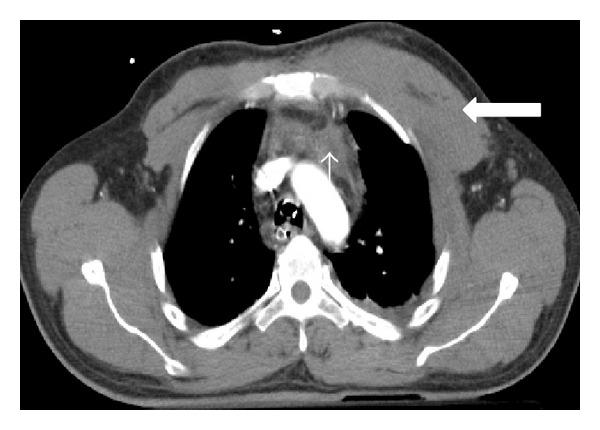

Imaging plays an essential part of chest trauma care. By definition, the employed imaging technique in the emergency setting should reach the correct diagnosis as fast as possible. In severe chest blunt trauma, multidetector computer tomography (MDCT) has become part of the initial workup, mainly due to its high sensitivity and diagnostic accuracy of the technique for the detection and characterization of thoracic injuries and also due to its wide availability in tertiary care centers. The aim of this paper is to review and illustrate a spectrum of characteristic MDCT findings of blunt traumatic injuries of the chest including the lungs, mediastinum, pleural space, and chest wall.

影像学在胸部创伤治疗中起着至关重要的作用。根据定义,在急诊环境中所采用的影像学技术应尽快得出正确诊断。在严重胸部钝性创伤中,多排螺旋计算机断层扫描(MDCT)已成为初始检查的一部分,这主要归因于该技术在检测和鉴别胸部损伤方面具有高敏感性和诊断准确性,还归因于其在三级医疗中心广泛可用。本文旨在回顾并阐述胸部钝性创伤包括肺、纵隔、胸膜腔和胸壁的一系列MDCT特征性表现。